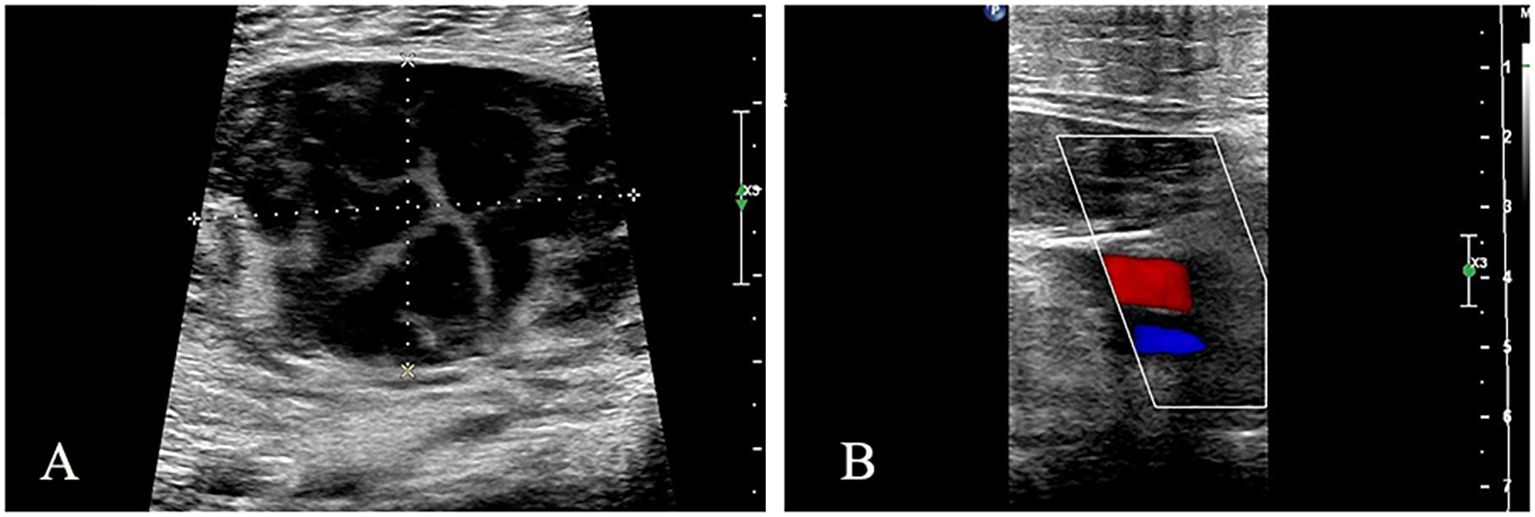

Abstract: Primary non-Hodgkin lymphoma (NHL) of the left lower extremity muscle is a rare exonodal lymphoma, accounting for less than 1% of all exonodal NHL. We report a rare case of intramuscular NHL of the left lower extremity and discuss its clinical features, diagnostic challenges, and treatment strategies with reference to the literature. The patient, an adult male, was treated for sudden swelling and pain in the left lower limb. Ultrasound examination revealed hypoechoic myometrium (hematoma considered), and ultrasound-guided puncture biopsy confirmed "primary CD5 + diffuse large B-cell lymphoma (leg type)"; the patient received 6 chemotherapy, and the symptoms were significantly relieved, but early local recurrence occurred; the clinical manifestations and imaging features of primary NHL in skeletal muscle lacked specificity, and the diagnosis depended on pathology and molecular analysis. Its pathogenesis may be related to direct invasion, hematogenous metastasis or primary muscle lesions. CD5 + diffuse large B-cell lymphoma (DLBCL) is aggressive and R-CHOP combined with radiotherapy is recommended, but prognosis is affected by age, LDH levels, and molecular characteristics such as TP53 mutations. Primary non-Hodgkin lymphoma in the muscle of left lower limb is very rare. It is difficult to diagnose it by imaging examination alone. It needs to be considered comprehensively by combining various examination methods. Pathology is the gold standard for diagnosis. Radiotherapy and chemotherapy are the first choice for treatment. It is very important to formulate reasonable treatment plan according to the results of pathology and molecular analysis.